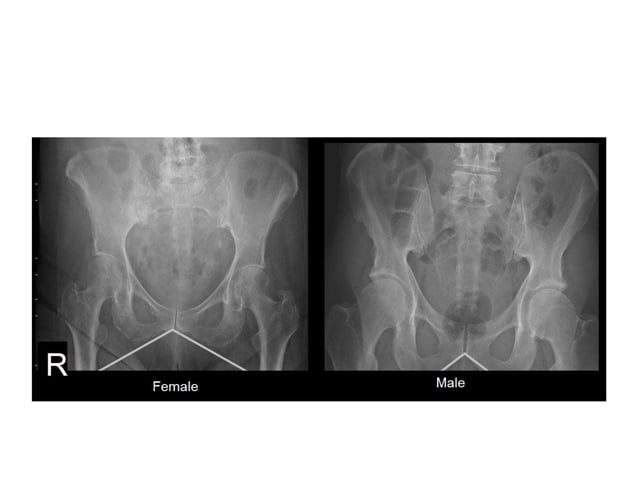

Pelvic Radiographs Pptx Although radiography can be used to image any orthopedic anatomy, this article focuses on positioning of the pelvic limbs. these tips are useful options for patients with many common orthopedic conditions, such as cranial cruciate ligament disease, patellar luxation, and hip dysplasia. Radiographic evaluation of pelvic limbs is fundamental to an orthopedic workup. this article outlines practical techniques to help with patient positioning. Dr. gabriela baers, a veterinary radiologist, discusses recommendations for and the importance of proper positioning for pelvic radiographs in ofa hip evaluations. Separate legs with lower leg pulled forward in a natural walking position, raise as needed. use sandbags straps to restrain front end, and wedge raise hind legs to create a square pelvis.

Pelvic Radiographs Pptx Dr. gabriela baers, a veterinary radiologist, discusses recommendations for and the importance of proper positioning for pelvic radiographs in ofa hip evaluations. Separate legs with lower leg pulled forward in a natural walking position, raise as needed. use sandbags straps to restrain front end, and wedge raise hind legs to create a square pelvis. Dr. gabriela baers, a veterinary radiologist, discusses recommendations for and the importance of proper positioning for pelvic radiographs in ofa hip evaluations. When a patient cannot tolerate extended leg positioning, the lateral view is preferred as it provides adequate visualization of the pelvis without requiring full extension. ofa & certification the orthopedic foundation for animals (ofa) evaluates hip dysplasia using pelvic radiographs, which is a hereditary condition affecting the hip joint. This article discusses the detrimental impact that an incorrectly positioned x ray can have on the accurate diagnosis of hip dysplasia or hip grading and certification. The purpose of this article is to review the three basic components of creating high quality pelvic radiographs of the dog and cat, including positioning, technique, and quality control of the final images.